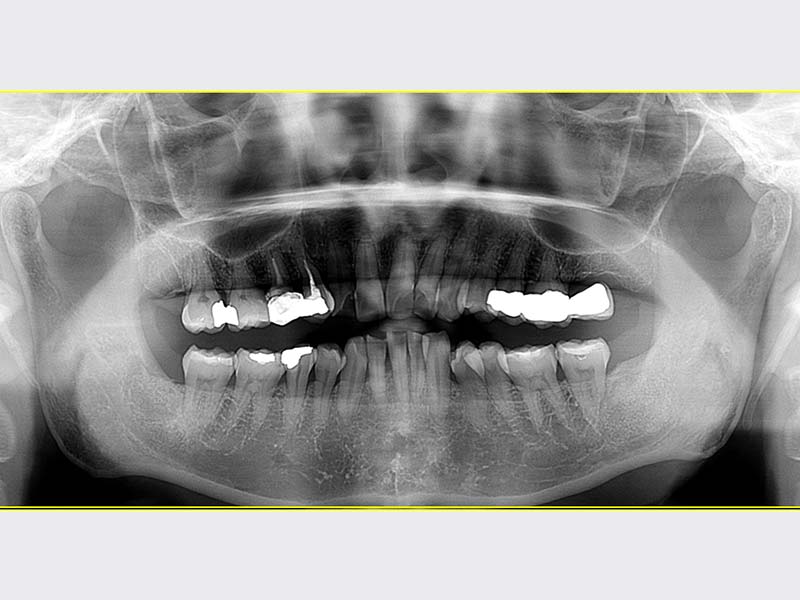

智齒手術

• 智齒手術